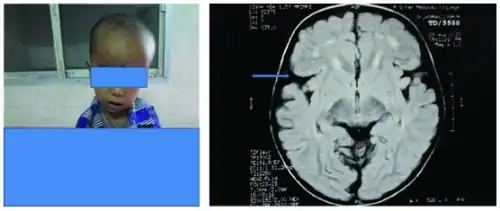

Babies with glutaric acidemia type 1 often are born with unusually large heads (macrocephaly). Macrocephaly is amongst the earliest signs of GA1. It is thus important to investigate all cases of macrocephaly of unknown origins for GCDH deficiency,[2][3] given the importance of the early diagnosis of GA1.[4] Macrocephaly is a "pivotal clinical sign" of many neurological diseases. Physicians and parents should be aware of the benefits of investigating for an underlying neurological disorder, particularly a neurometabolic one, in children with head circumferences in the highest percentiles.

Normally in MRI the Sylvian fissure is operculated, but in glutaric acidemia type 1, it is not operculated. In many areas, GA1 is included in newborn screening panels. Elevated glutarylcarnitine can be detected by mass spectrometry in a dried blood spot collected shortly after birth. After a positive screening result, confirmatory testing is performed. This includes urine organic acid analysis, looking for glutaric acid and 3-hydroxyglutaric acid. Plasma and urine acylcarnitine analysis can also be informative. Molecular analysis, including gene sequencing and copy number analysis of GCDH can be performed to confirm the diagnosis. Molecular testing can also provide information for family planning and prenatal testing, if desired.